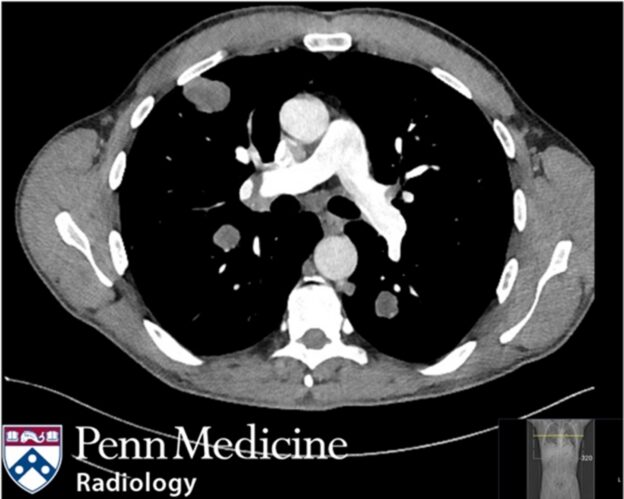

24-year-old man with shortness of breath and unintentional weight loss

A 24-year-old man presented with a three-month history of shortness of breath and unintentional weight loss.